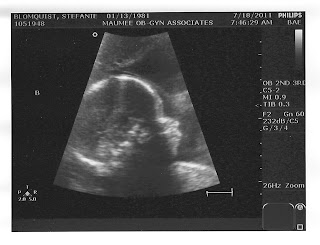

Almost Week 26 and another Ultrasound

25 weeks and 5 days today.  A little more than 20 pounds gained so far.  Doing well and the cerclage looks good according to the doctor.

Cole is 2 lbs!

Nolan is 2.2 lbs!